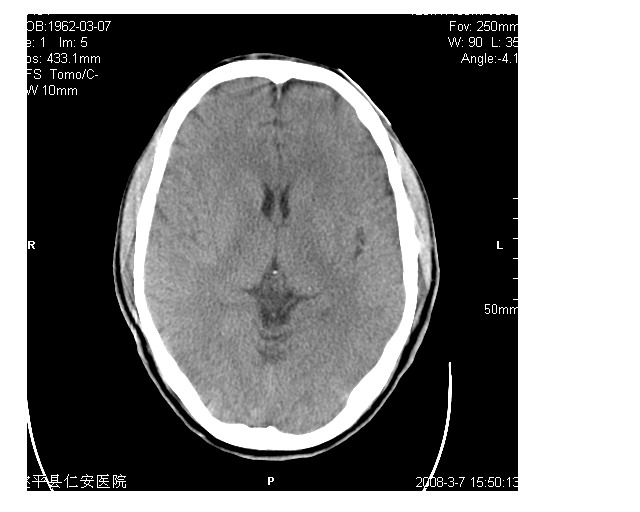

男36岁,外伤进行ct检查时发现脑实质及脑室旁多个细结节状影。是囊虫病吗?

脑内及脑室内可见多发性结节影,脑囊虫病不能除外,建议强化扫描或mri。

有吗?我只看见图象噪声致颗粒粗大,未见异常。建议加大mas

只看到左侧脑室内多发钙化.可以做结合补体实验啊.但未必阳性.还是隔期复查.mr 也未必定啊.